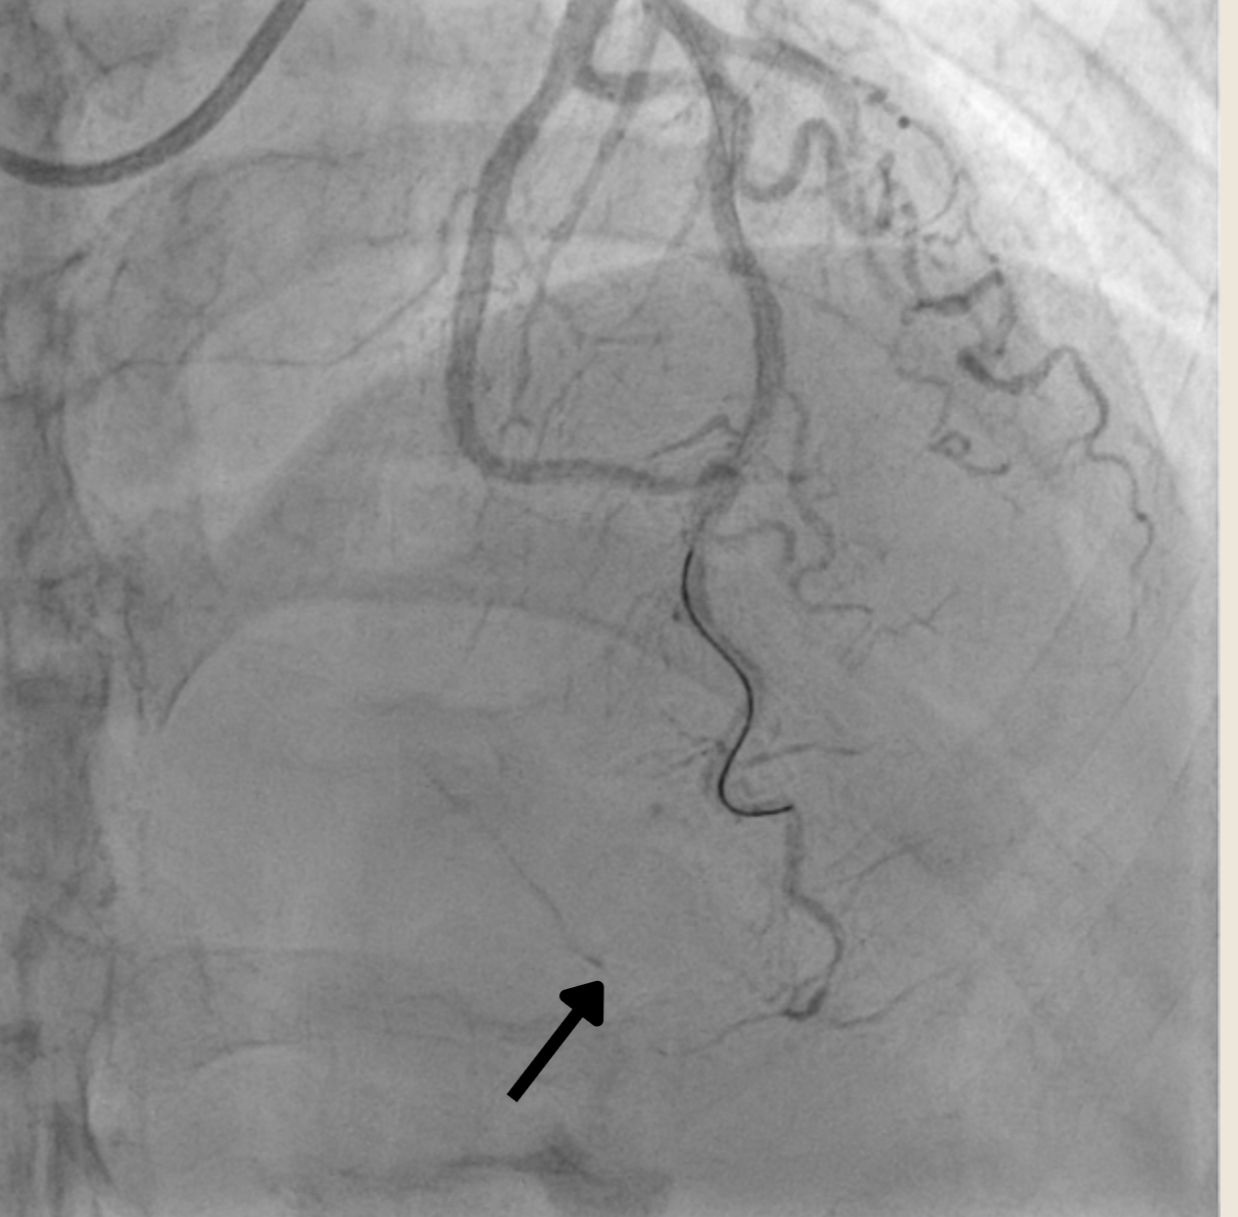

Angiography revealed single vessel disease. Left anterior descending artery (LAD) showed mild stenosis of proximal-mid part and total occlusion of the distal part Left circumflex (LCx) artery and The right coronary artery (RCA) showed minimally diseased.

PCI was conducted using guide catheter EBU3.5/6F, A 0.014-inch floppy guidewire and was placed in distal LAD. After sliding the distal lesion with semicompliant 1.5 x 15mm, we encountered distal perforation type V with Ellis type III. Multiple prolonged ballon inflation was done using semicompliant 2.0 x 15mm at 4 atm but the perforation jet persisted. We decided to do microcatheter-assisted absorbable suture embolization technique with chromic catgut 3.0. The perforation was successfully managed. Echocardiography evaluation revealed Concentric Left Ventricular Hyperthrophy with normal LVEF without signs of pericardial effusion. Patient was dismissed from hospitalization without further complication.